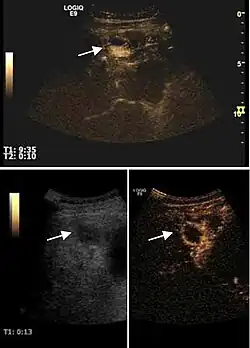

Early hepatocellular carcinoma (Early HCC)

The suggestive appearance of early HCC on 2D ultrasound examination is that of hypoechoic nodule, with distinct pattern, developed on cirrhotic liver. Hypoechoic appearance is characteristic of moderate/poorly differentiated HCC, with low or absent fatty changes. Rarely, HCC may appear isoechoic, consist of a tumor type with a higher degree of differentiation and therefore with slower development. Another common aspect is "bright loop" or "nodule-in-nodule" appearance, hypoechoic nodules in a hyperechoic tumor.

Spectral Doppler characteristics of early HCC overlap those of the dysplastic nodule, as they are represented by the presence of portal venous signal type or arterial type with normal RI (well differentiated HCC) or increased RI (moderately or poorly differentiated HCC). The CFM exploration identifies a chaotic vessels pattern.

On CEUS examination, early HCC has an iso- or hypervascular appearance during the arterial phase followed by wash out during portal venous and late phase. There are studies showing that the wash out process is directly correlated with the size and features of neoplastic circulatory bed. Thus, highly differentiated HCC illustrates the phenomenon of late or even very late "wash out" while poorly differentiated HCC has an accelerated wash out at the end of arterial phase. It is therefore mandatory to analyze all these three phases of CEUS examination for a proper characterization of liver nodules. Tumor wash out at the end of the arterial phase allows the HCC diagnosis with a predictability of 89.5%. Some authors consider that early pronounced contrast enhancement of a nodule within 1–2 cm developed on a cirrhotic liver is sufficient for HCC diagnosis. These results prove that for a correct characterization of the lesions it is necessary to extend the examination time to 5 minutes or even longer.